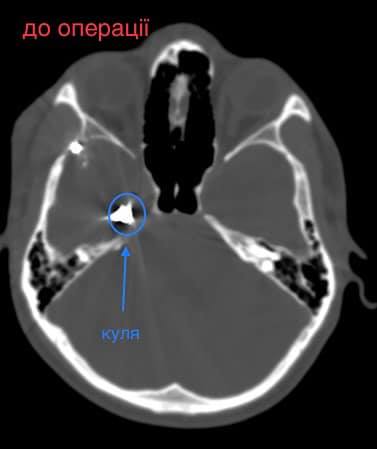

Як повідомив у Фейсбуці нейрохірург дитячої лікарні Михайло Ловга, у хлопця була куля в голові, що призвела до руйнації скроневої кістки та частини головного мозку.

«Ми виконали невідкладну операцію і вилучили стороннє тіло, видалили пошкоджені тканини і відновили цілісність збережених тканин. Добре, що куля зупинилась в 1 см від надзвичайно важливої судини і права скронева частка (яка пошкодилась в результаті травми) – функціонально незначима. Інакше, наш козак був би зовсім іншим, назавжди», – написав Михайло Ловга.